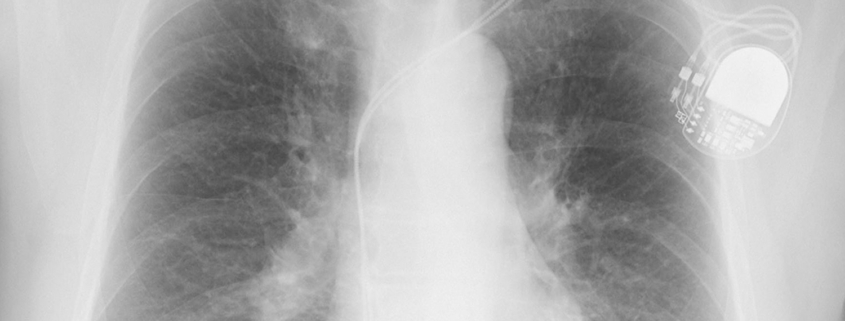

Elektrostimulator srca (engl. pacemaker) je električni uređaj koji se ugrađuje ispod kože pacijenta kako bi održavao ili povratio normalan srčani ritam.

Srčana resinkronizacijska terapija (engl. Cardiac resynchronization therapy – CRT) je zahvat kojim se liječe neke vrste srčanog zatajivanja. Srčano zatajivanje je stanje kada srce ne istiskuje („punpa“) dovoljno krvi.

Ugradbeni kardioverter defibrilator (engl. implantable cardioverter defibrilator – ICD) je elektronički uređaj sličan elektrostimulatoru srca koji se ugrađuje ispod kože pacijenta.